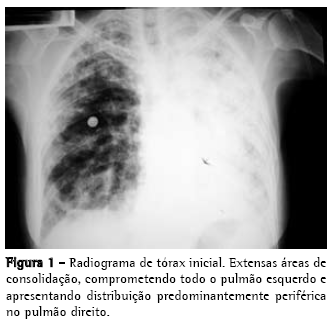

Radiograma e tomografia computadorizada de tórax iniciais, nas Figuras 1 e 2;

Ultra-sonografia de tórax: derrame pleural à esquerda, sem septações, que se estendia da base ao terço superior do hemitórax esquerdo;

Sintomas respiratórios são comuns na SEM e podem estar presentes em até 80% dos pacientes,(14) inclusive como manifestação única. Em uma série de 1.531 casos,(15) tosse ou dispnéia estiveram presentes em 611 deles (59%), e em outro estudo,(16) com 118 pacientes, foram encontrados sintomas respiratórios em 64%, alterações radiológicas em 16% e derrames pleurais em 15%. O acometimento pulmonar confere pior prognóstico e alguns pacientes podem evoluir para insuficiência respiratória aguda.(3,4,17) Os exames complementares, em geral, evidenciam leucocitose e eosinofilia (valores superiores a 3.000/mm3 são mais sugestivos).(11) O radiograma de tórax pode ser normal, apresentar opacidades intersticiais lineares ou reticulonodulares, consolidações pulmonares difusas e derrame pleural.(3,4,10) Os derrames pleurais podem aparecer em até um terço dos casos, e geralmente são exsudatos eosinofílicos.(4,10,16)